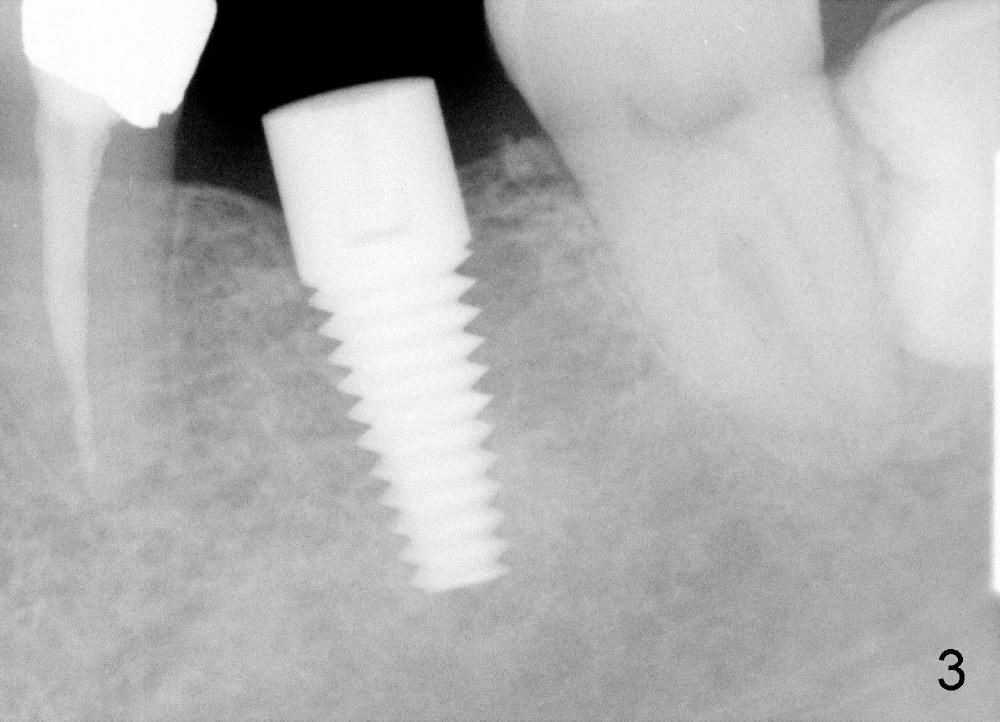

Mr. Zhou is in his fifties. Finally he starts implant restoration. But he has financial constraint. It appears that implant restoration at the site of #19 is the most rewarding in term of restoration of his mastication with a single implant (Fig.1). The implant is apparently placed at the proper level (Fig. 2: I, 6x17 mm). The implant is osteointegrated with minimal bone resorption at crest six months later (Fig.3). The teeth #15 and 18 cannot occlude when 4.5x5 mm abutment (Fig.4: A) is placed at #19 implant (<). It takes a while to trim the unipost from the top gradually in order to let #15 and 18 have normal occlusal contact (Fig.5 mirror image). By that time, the abutment is approximately 2.5 mm tall.

It has never occurred to me that the abutment can be truncated with a fissure bur. How can we avoid cutting too short? Retention of crown may be affected if the abutment is too short.